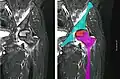

Front X-ray of right knee of an adolescent (epiphyseal plates are open): arrows point to avascular necrosis and developing osteochondritis dissecans in the outer medial condyle of femur

In the early stages, bone scintigraphy and MRI are the preferred diagnostic tools.[18][19]

X-ray images of avascular necrosis in the early stages usually appear normal. In later stages it appears relatively more radio-opaque due to the nearby living bone becoming resorbed secondary to reactive hyperemia.[2] The necrotic bone itself does not show increased radiographic opacity, as dead bone cannot undergo bone resorption which is carried out by living osteoclasts.[2] Late radiographic signs also include a radiolucency area following the collapse of subchondral bone (crescent sign) and ringed regions of radiodensity resulting from saponification and calcification of marrow fat following medullary infarcts.